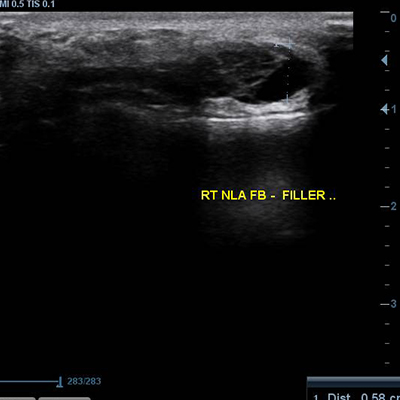

[얼굴이물질제거] 17.01.19 - 이물질제거 - 전후사진

17.01.19 - 이물질제거 - 전후사진